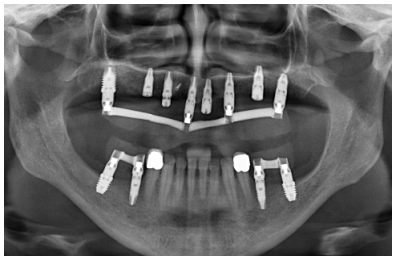

Cuatro meses después de la cirugía inicial de regeneración del maxilar se lleva a cabo un nuevo Cone-beam dental, en el que se planifica la siguiente fase de la cirugía en función de la ganancia ósea que se ha logrado con los injertos en bloque y la técnica de Split en dos fases. En las imágenes podemos observar como en las zonas de máxima atrofia, donde se colocan los bloques se ha logrado una anchura que triplica la inicial (Figuras 19 y 20). En la apertura del colgajo se observa como las imágenes del TAC de planificación se corresponden con la realidad, y además que la zona tratada mediante Split en dos fases ha logrado también una anchura de cresta que ahora permite la retirada de los implantes transicionales y la inserción de nuevos implantes en esta posición, con una mejor situación de partida y eje para la confección posterior de la prótesis (Figuras 21-22). Se procede a la inserción de los implantes y se realiza una prótesis provisional de carga progresiva apoyada en los implantes colocados en la primera fase quirúrgica. De este modo, la paciente puede tener una prótesis fija sobre implantes que servirá para ir dando forma a los provisionales en cuanto a estética y función de cara a la prótesis definitiva (Figuras 23-24).

Cuatro meses después se procede a la carga de los implantes insertados en esta segunda fase quirúrgica. De nuevo se opta por unas segundas prótesis provisionales de carga progresiva, elaboradas del mismo modo que las anteriores Tres meses después la oclusión está preparada para la confección de la prótesis definitiva, por lo que se transforma la prótesis en una prótesis metal-cerámica, atornillada sobre transepitelial confeccionada mediante cad-cam (Figuras 25-26). La paciente ha recuperado la función demandada, así como la corrección de la oclusión de la prótesis completa, que presentaba una mordida cruzada lateral derecha con disminución de la dimensión vertical al inicio del tratamiento. La paciente acude a sus revisiones y el tratamiento se mantiene estable tal como se muestra en las imágenes tomadas a los 10 años de seguimiento (Figuras 27-28).